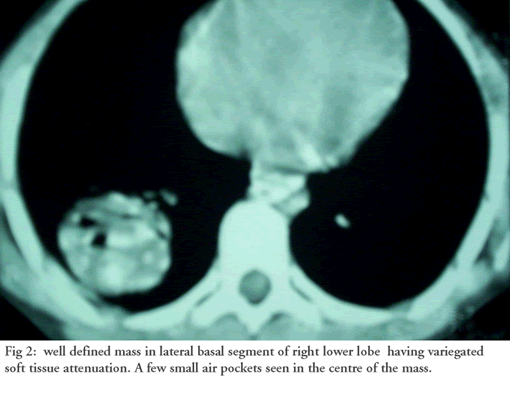

In the evening of July 1, 2005 a ten-year old child was brought to the emergency wing of the Government Medical College, Hospital Jammu in north India with history of two bouts of hemoptysis (each of 200 to 300 mls) on the morning of admission. He initially coughed out dark clotted blood, followed by frothy bright red blood.  Examination revealed pallor and bronchial breathing & crepitance in the right infrascapular area. A previous chest x-ray in May 2005 (CXR Figure 1) and contrast enhanced computed tomography chest (CECT, Figure 2) revealed a variegated soft tissue mass in the right lower lobe.

Figure 1: Rounded radio opacity in right lower lobe. Figure 2: Well defined mass in right lower lobe having variegated soft tissue attenuation. A few small air pockets seen in the center of the mass.